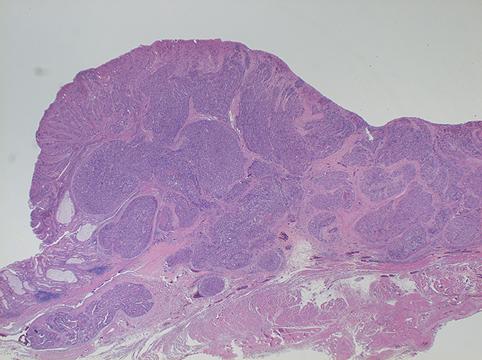

疾患(病理主体)の分類悪性上皮性腫瘍/腺癌

部位(臓器別)胃(部位)/噴門

検査方法ミクロ

腫瘍の肉眼分類2型(潰瘍限局型)/

病変の最大径(ミリ)30〜34

腫瘍の深達度ss(a1)